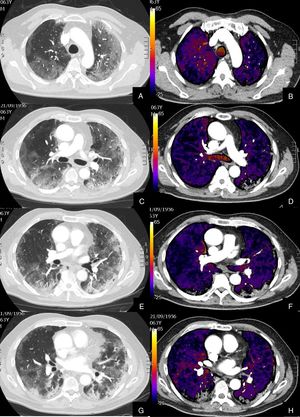

Se diagnosticó de TEP agudo a 22 (27,16%) pacientes, de los cuales, 11 (50%) presentaban TEP central y periférico y 11 (50%) sólo TEP periférico (fig. 2). El TEP fue bilateral en 13 (59,09%) pacientes. En tres (13,63%) pacientes se observó consolidación periférica triangular en el territorio de las arterias ocluidas, sugestiva de infarto pulmonar, hallazgo recientemente reportado en literatura en estos pacientes26.

Paciente con alta sospecha de COVID-19, con D-dímero de 80.000, disnea y fiebre de 15 días de evolución.

Imágenes axiales de la angiografía pulmonar con TC y mapa de yodo en ventana de pulmón (A, C, E) desde cayado hasta lóbulos inferiores y la correlación con el mapa de yodo (B, D, F) e imágenes axiales (G y H) en ventana de mediastino.

Parénquima con extensa afectación en «crazy paving» subpleural y peribroncovascular de predominio en segmentos posteriores, con TEP agudo en arteria lobar inferior derecha y segmentarias inferiores derechas (flechas blancas) y leve hipoperfusión periférica en LID (áreas parcheadas azules) en relación con el tromboembolismo.